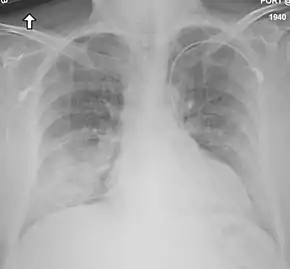

Chest X-ray of a case of MERS

Chest X-ray findings tend to show bilateral patchy infiltrates consistent with viral pneumonitis and acute respiratory distress syndrome (ARDS). Lower lobes tend to be more involved. CT scans show interstitial infiltrates.[24]